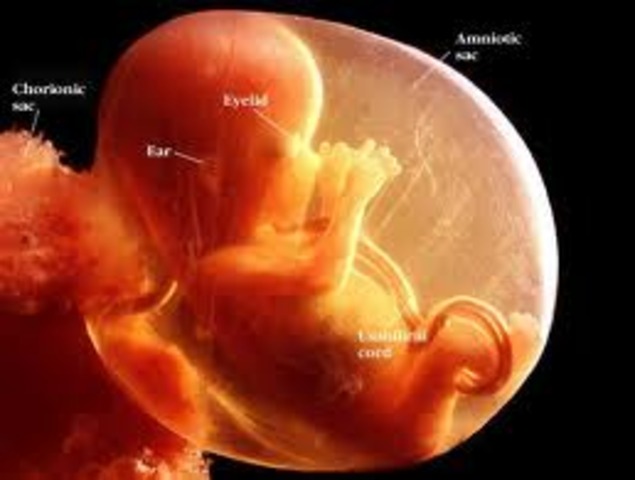

• Month 3

Month 3

• The baby is now about 1 inch long.

• The nostrils, mouth, lips, teeth buds, and eyelids have begun to form.

• The fingers and toes are almost complete.

• All of the organs are present now, although immature.